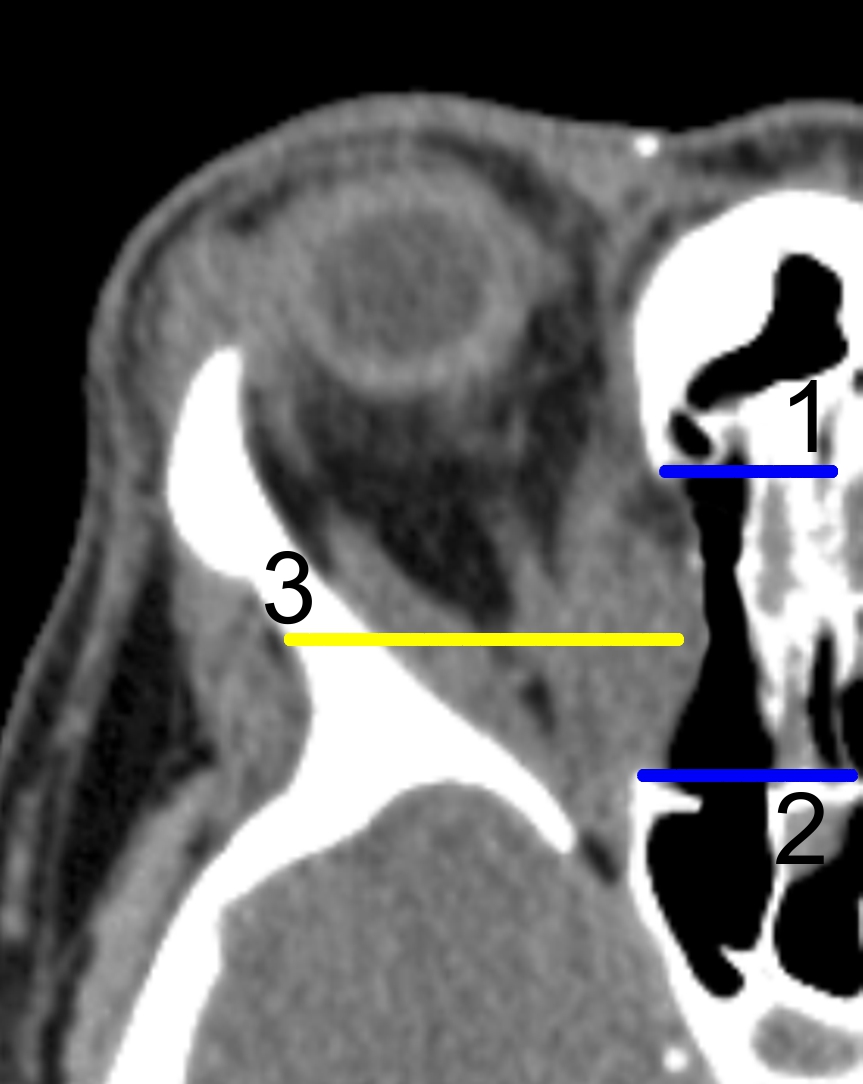

У пациентов регресс экзофтальма после ТЭДО составил от 3,5 до 6,5 мм (рис. 1). При исходных средних 25,4 мм экзофтальм уменьшился в среднем на 5,1 мм, что составило в среднем 18,8 мм (р < 0,05). МСКТ-исследование демонстрировало пролабирование мягких тканей орбиты в сформированное костное окно (рис. 2).

Рис. 2. Компьютерная томография пациентки после ТЭДО. Аксиальный срез. Отмечены границы наложенного костного окна (1, 2); пролабирование орбитальных тканей в сформированное костное окно (3).

1. Рис.2. Компьютерная томография пациентки после ТЭДО, аксиальный срез. Отмечены границы наложенного костного окна (1,2); пролабирование орбитальных тканей в сформированное костное окно (3)

4. Рис. 2. Компьютерная томография пациентки после ТЭДО. Аксиальный срез. Отмечены границы наложенного костного окна (1, 2); пролабирование орбитальных тканей в сформированное костное окно (3).